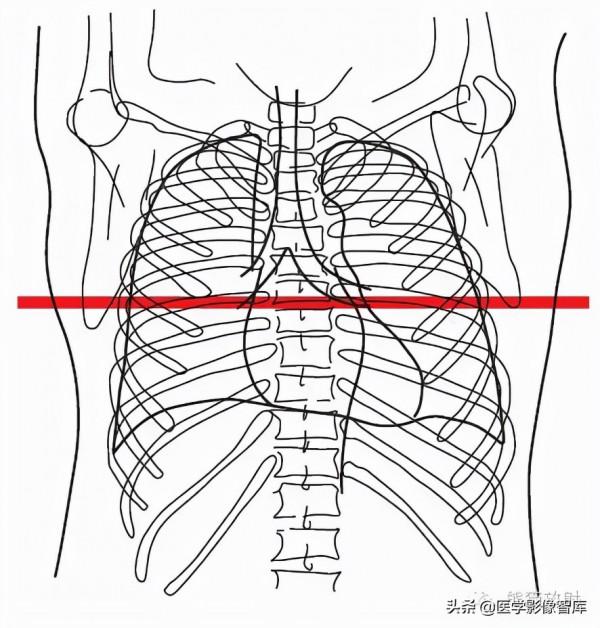

2. Rib 肋骨